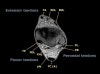

MRI : 장무지굴근건 건초염(Flexor hallucis longus tenosynovitis)